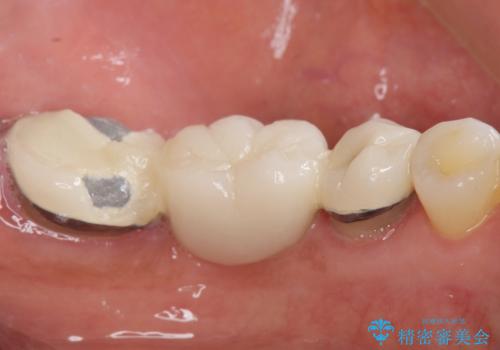

- 奥歯の痛みを主訴に来院された患者様です。

精査したところ、ブリッジの支台歯となっている左下の奥歯(左下7)は大きなう蝕により神経が死んでいました。

根管治療後、メタルボンドブリッジによる補綴治療を行いました。